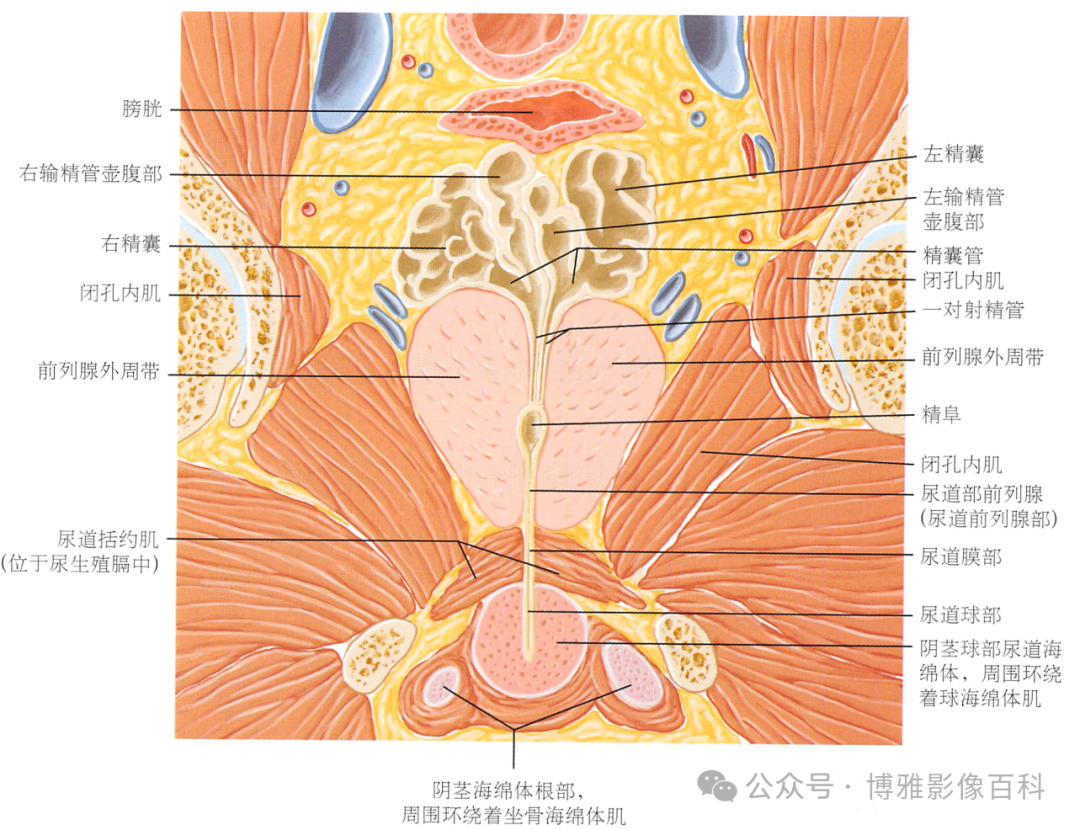

MR 解剖学

前列腺良性增生患者的轴向T2 图像,其他方面正常。外周带是一薄层均匀的高信号,边界清晰连续性的低信号包膜。移行带通常表现为不均匀中等信号,病灶被边界清楚的BPH良性前列腺增生结节所取代。精囊具有均匀T2高信号。未见淋巴结肿大。